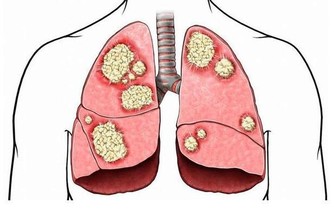

第二道坎、50~70歲:腫瘤關

50歲後,人體激素水平開始下降,免疫功能逐漸降低,

原本能被免疫系統控制的癌基因或突變細胞,也會逐漸癌變。

有的癌症可能早在多年前就潛伏下來,到了40~50歲以後才發病。

防癌至少要提早20年。

也就是說,過了35歲就應每年做1次防癌體檢,尤其是有腫瘤家族史的人。